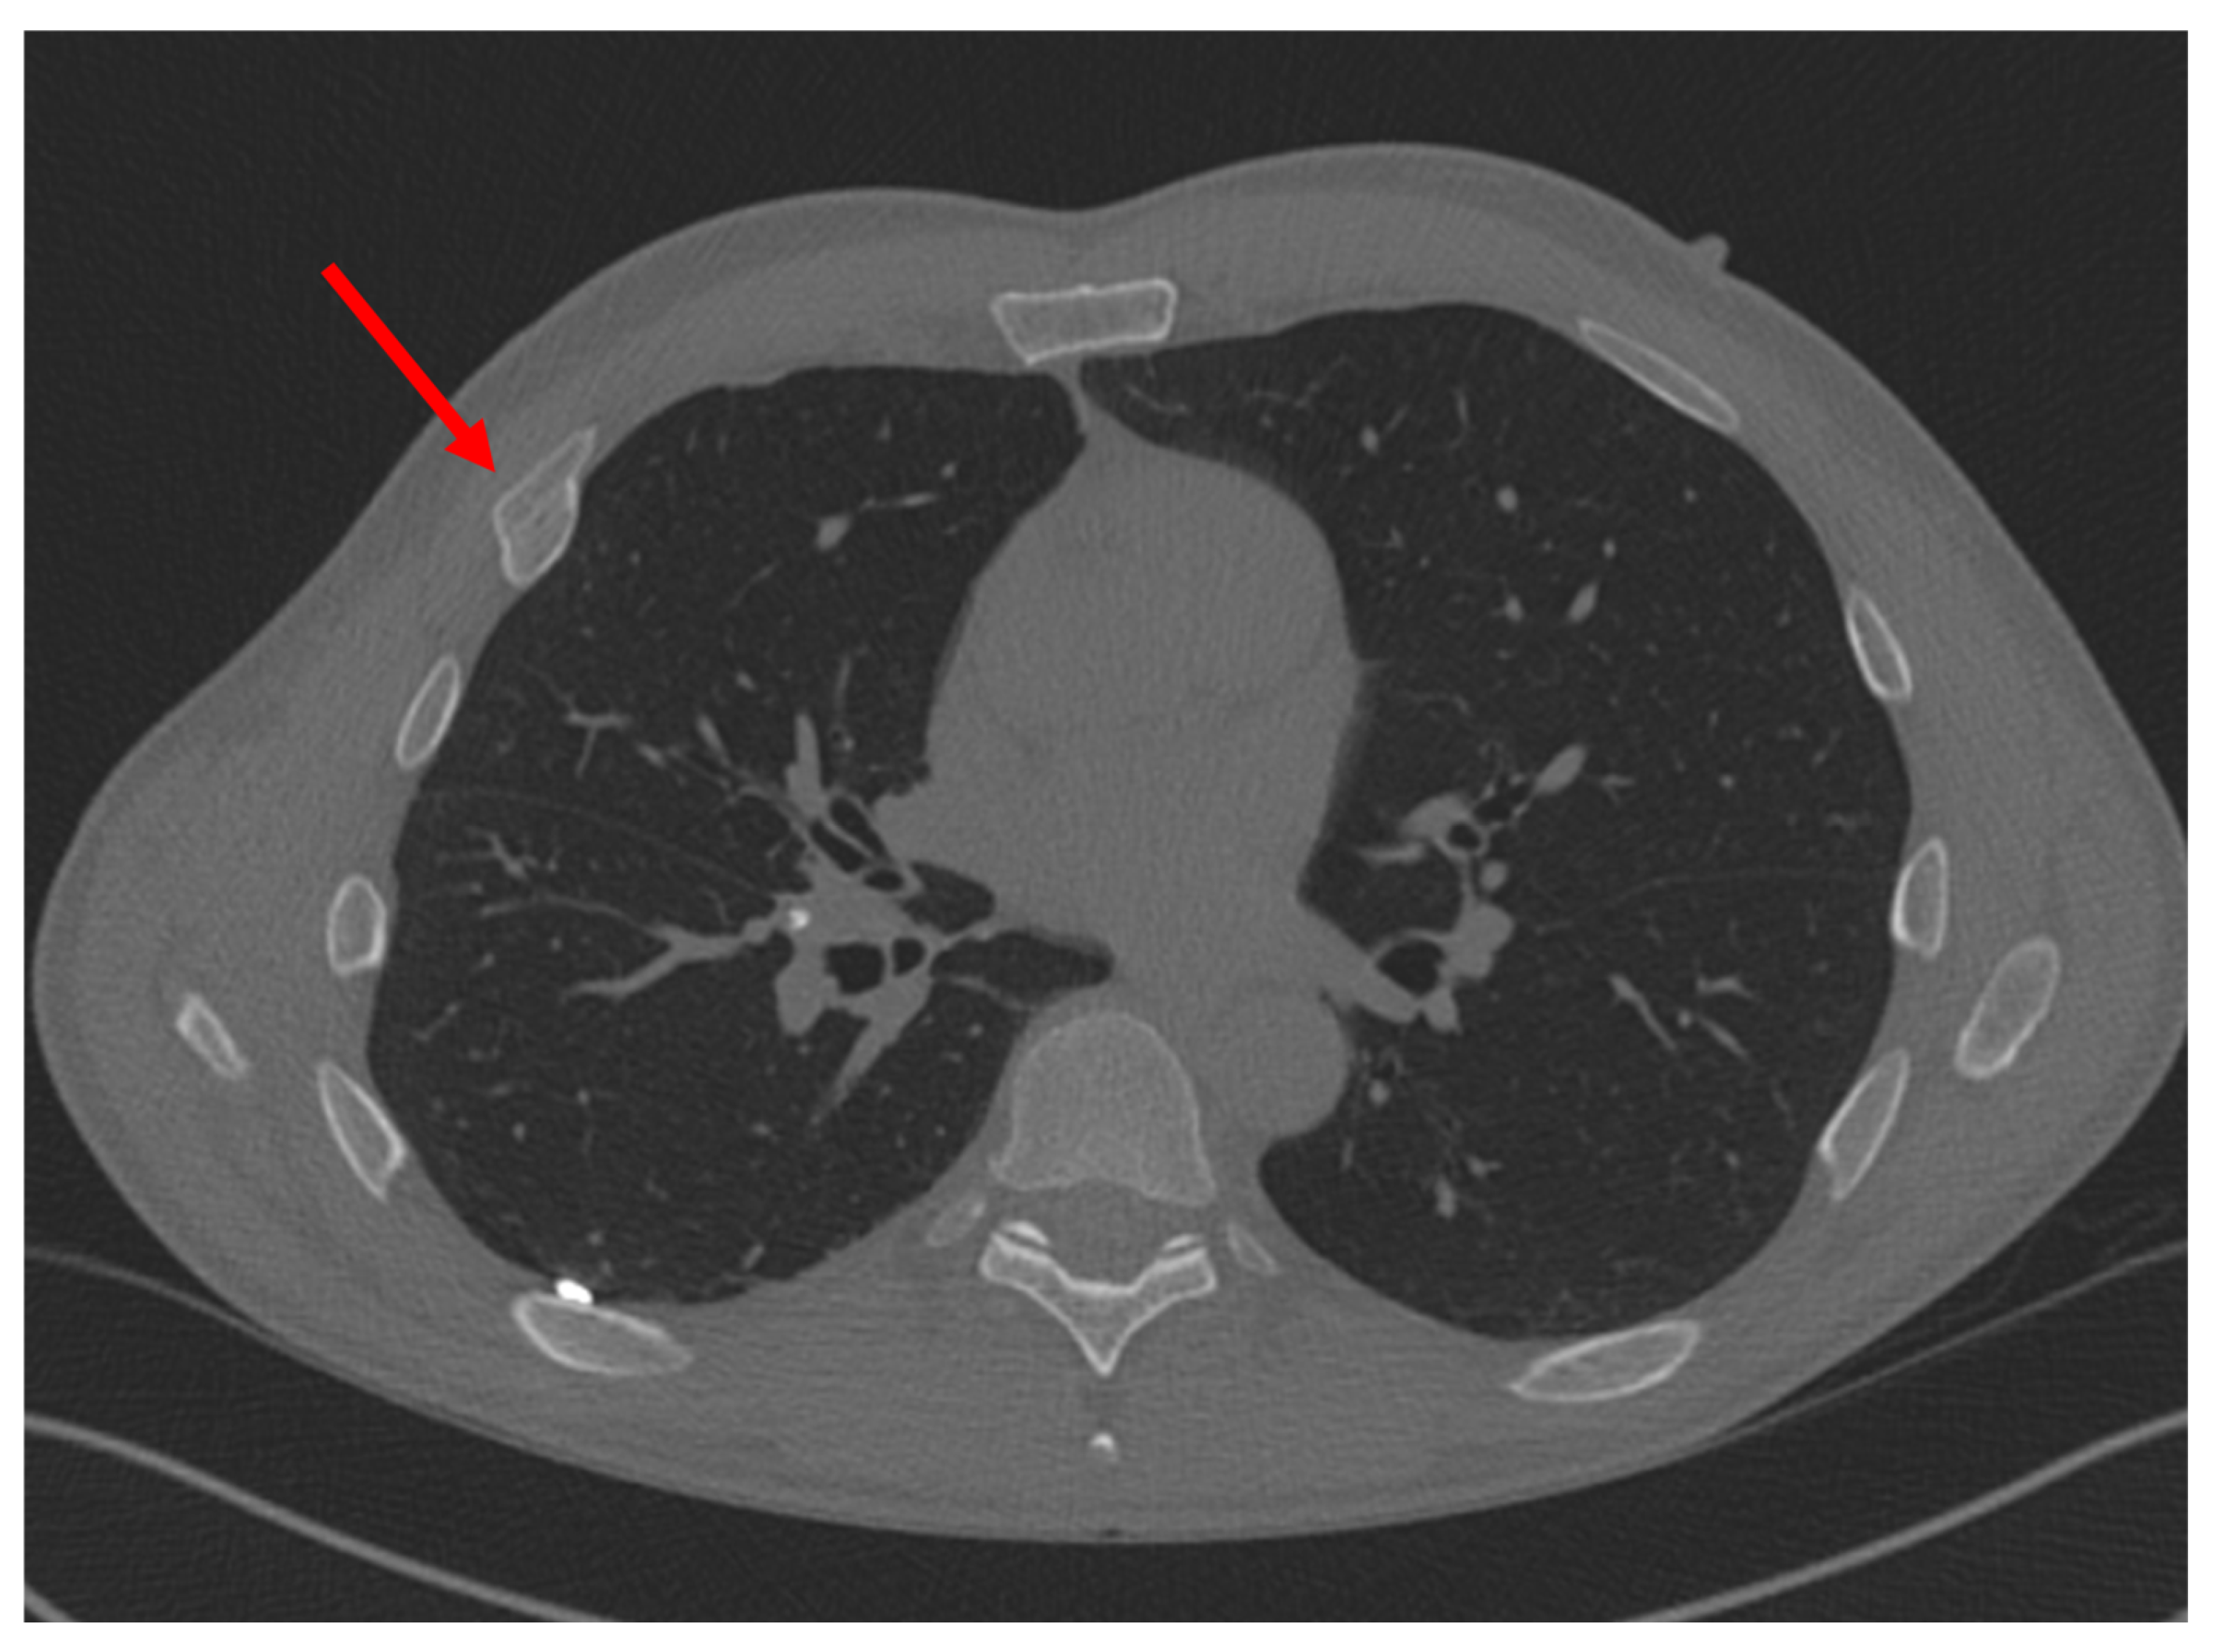

Figure 3.

Malunion fracture of the 4th rib. Red arrow points to the location of injury.